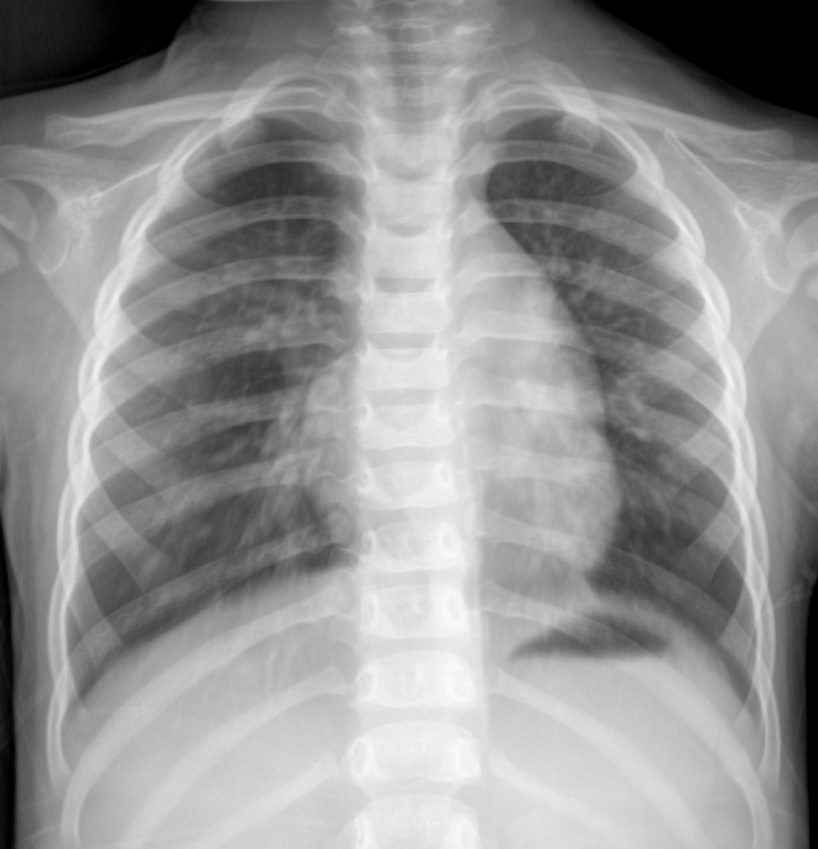

标题: PED3047:两岁,咳嗽3天 。

先心病,双侧肺血增多;建议彩超检查。

心腰膨隆,肺血增多,考虑先心病,建议结合彩超检查。

双肺纹理增多,肺血管从分布,主动脉结小,肺动脉段突出。 先心病?结合彩超

考虑先天性心脏病;请结合临床听诊及心脏超声检查。

2、左上纵隔影增宽考虑为胸腺影,建议ct。